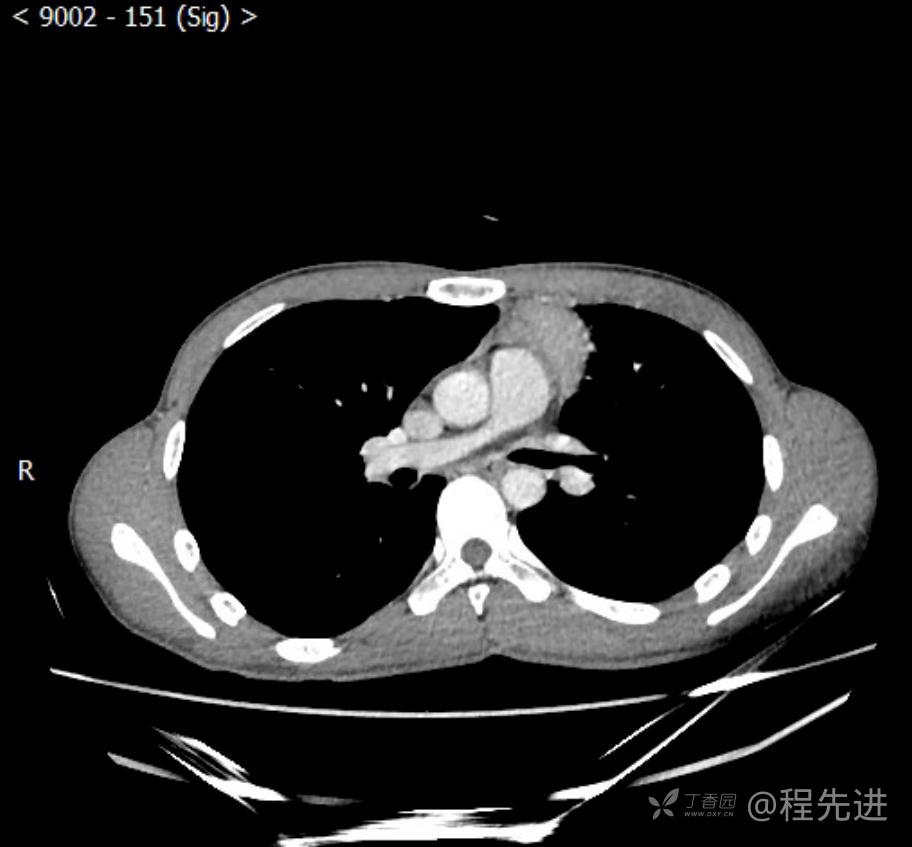

主诉:反复咳嗽1月,发现“纵隔”占位半月,乏力10余天。

现病史:患者1月前无明显诱因出现咳嗽,以夜间为著,伴有少量白痰,无发热,无胸痛、咯血,无痰中带血,未予重视,半月前外院行胸部CT检查发现“左前上纵隔”占位,未予进一步检查及治疗。近10余天自觉乏力,逐渐加重。